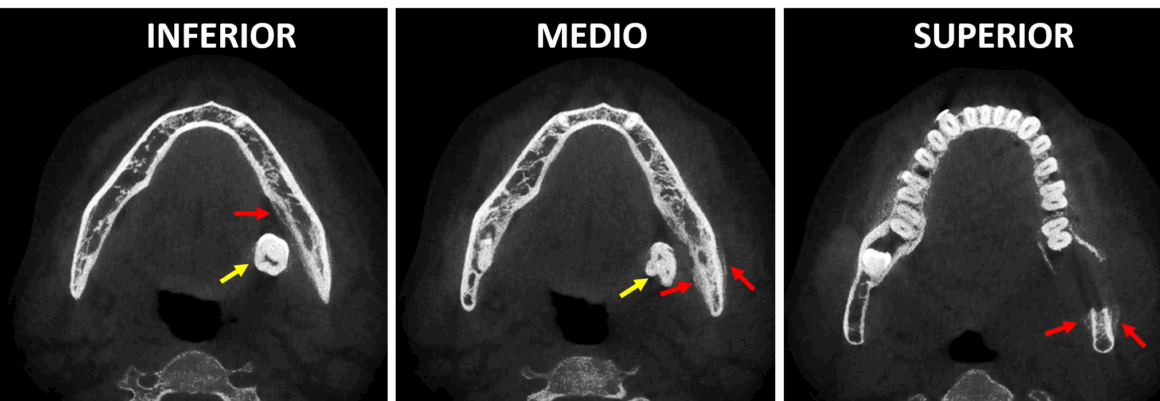

En cortes transaxiales (Fig.2) y en cortes axiales (Fig.3) se observa el órgano dentario 38 localizado por lingual en el tejido blando adyacente al cuerpo mandibular (flechas amarillas), donde se observa también la ausencia de la tabla ósea lingual, asi como la ausencia parcial de la tabla ósea externa en relación con una imagen hipodensa amplia sugerente de un lecho quirúrgico que compromete también el cortical superior del conducto dentario inferior. Nótese las tenues imágenes hiperdensas dependientes de la tabla externa e interna (flechas rojas) sugerentes de una neoformación ósea compatible con una reacción perióstica.